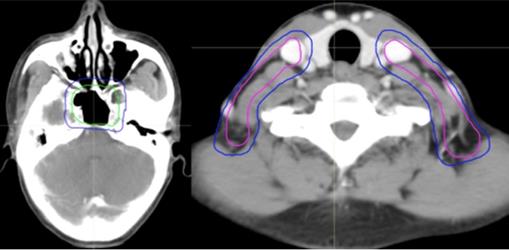

Based on the orderly stepwise pattern of tumor spread, we designed three or four risk target volumes in the pathway of NPC tumor invasion including the peripheral (Figure 1A), upper, and lower structures (Figure 1B). The corresponding target volumes included high-risk planning target volume of nasopharyneal GTV (PGTVnx) or planning target volume of GTV in cervical lymph nodes (PGTVnd) encompassing GTV of nasopharynx (GTVnx) or GTV of cervical lymph nodes (GTVnd), intermediate-risk planning target volume of nasopharyx (PTVnx) or planning target volume of neck area (PTVna) encompassing CTV of nasopharynx (CTVnx) or CTV of neck area (CTVna), and low-risk planning target volume (PTV) encompassing CTV. If the retropharyngeal lymph nodes (RLNs) were large or resistance to IC, we add a higher risk target volume for PTV of GTV in retropharyngeal lymph nodes (PGTVrpn) encompassing GTV of retropharyngeal lymph nodes (GTVrpn). The relationship of the three to four risk tumor volumes such as PGTVnx (PGTVrpn), PGTVnd, PTVnx, PTVna, and PTV is shown in Figure 1.

Figure 1

The different risk target volumes. (A) Cross section; (B) coronary position. Red: PGTVrpn; orange: PGTVnx; yellow: PGTVnd; green: PTVnx; pink: PTVna; blue: PTV. Abbreviations: PGTVrpn: planning target volume of GTV in retropharyngeal lymph nodes; PGTVnx: planning target volume of nasopharyngeal GTV; PGTVnd: planning target volume of GTV in cervical lymph nodes; PTVnx: planning target volume of nasopharynx; PTVna:planning target volune of neck area; PTV: planning target volume.